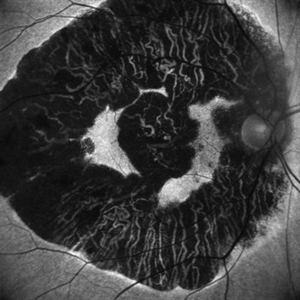

Geographic Atrophy- Retro Mode

May 10 2020 by Gayathri Mohan

Image of a patient with geographic atrophy taken in retro mode. The deeper choroidal vessels are prominently seen.

Photographer: Gayathri Mohan, Retina Foundation

Imaging device: Mirante, Nidek

Condition/keywords: geographic atrophy, retro